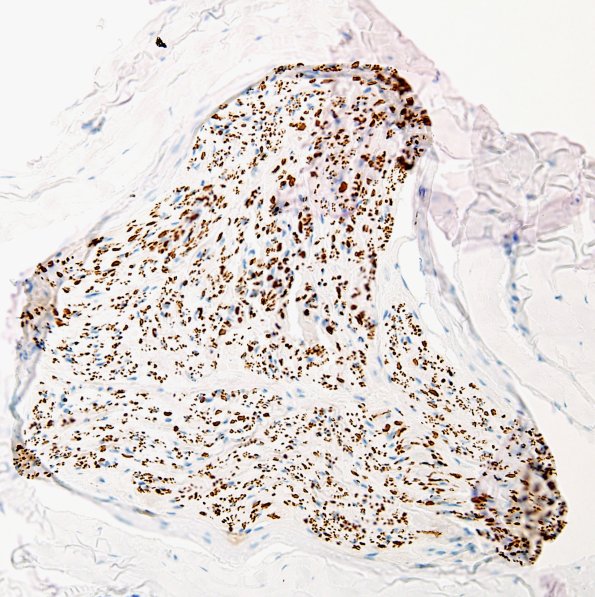

4B1,2 Some fascicles have a well preserved complement of axons. (NF IHC)